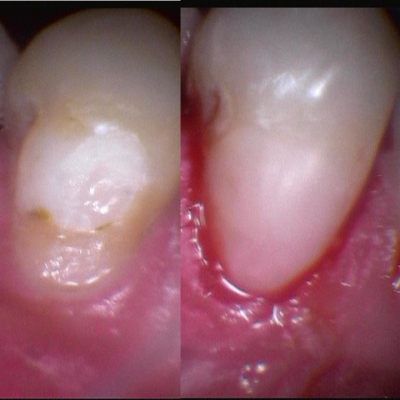

Gallery

Galeria